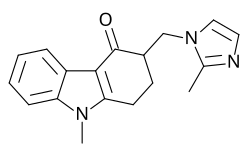

Entaktogene und Empathogene

Als Entaktogene (Adjektiv entaktogen, „das Innere berührend“, aus griechisch en, „innen“, lateinisch tactus „berührt“) und Empathogene (empátho; altgriechisch ἐμπάθω, „mitfühlen“; vergleiche Empathie; -gen von altgriechisch γένεσις, génesis, „Entstehung“) werden psychoaktive Substanzen bezeichnet, unter deren Einfluss die eigenen Emotionen intensiver wahrgenommen werden. Der Terminus Entaktogen wurde von dem US-amerikanischen Chemiker David E. Nichols in den 1980er Jahren eingeführt.[98] Zu jener Zeit wurden diese Substanzen auch in der umstrittenen Psychotherapie mit Psychedelika eingesetzt, da sich der Patient seiner eigenen Psyche besser bewusst wird und somit der Zugang zu seinem Unterbewussten erleichtert wird. Beide Termini werden synonym verwendet. Viele Entaktogene, wie z. B. 3,4-Methylendioxyamphetamin (MDA), 3,4-Methylendioxy-N-methylamphetamin (Ecstasy, MDMA), 3,4-Methylendioxy-N-methylcathinon (bk-MDMA, MDMC) wirken als Releaser (Ausschütter) der endogenen Monoamin-Neurotransmitter Serotonin und Noradrenalin, was zu einem unüblich erhöhten Spiegel dieser Botenstoffe im Gehirn führt.[99]